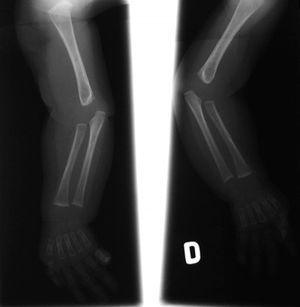

El EEG muestra una pobre estructuración del trazado de fondo, con múltiples descargas de punta-onda en ambas áreas temporales. En la serie esquelética destacan la reacción perióstica en huesos largos y una deformidad en copa de las metáfisis radiales (fig. 2). La densitometría ósea es normal. La RM y angiorresonancia cerebrales revelan un retraso de la mielinización, un infarto isquémico reciente en pálido derecho y unas arterias vertebrales elongadas y tortuosas (fig. 3).

Figura 2. Radiografía simple que muestra la reacción perióstica en huesos largos y una deformidad en copa de ambas metáfisis radiales.